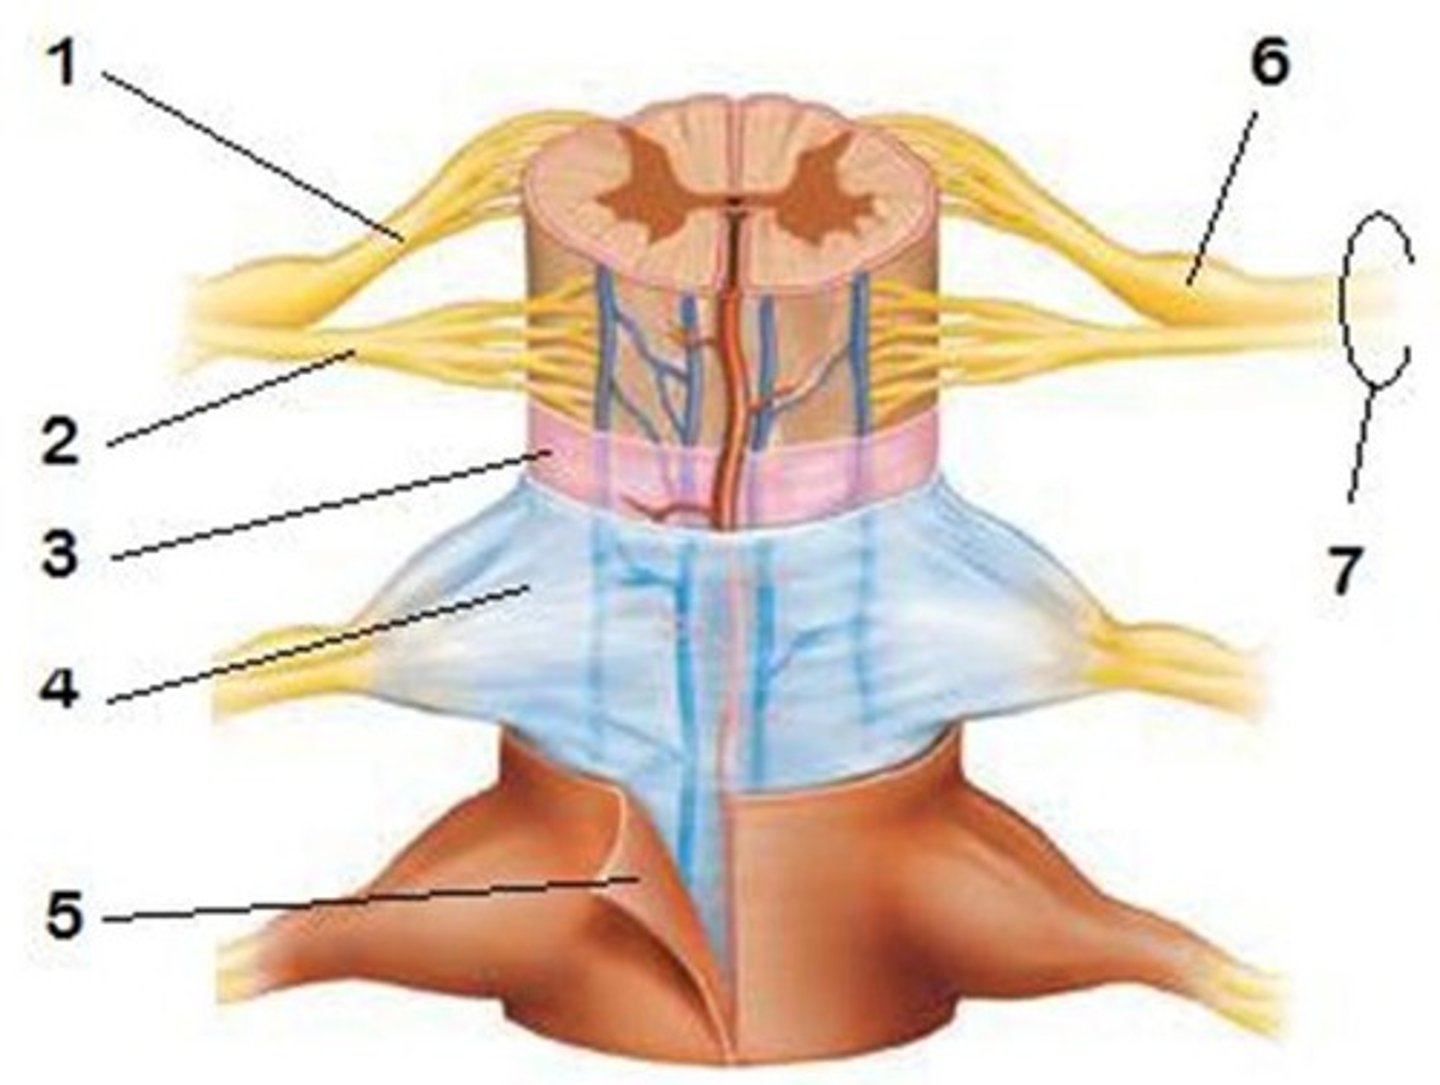

spinal meninges

dura mater, arachnoid mater, pia mater (PAD to protect the spinal cord from deep to superficial)

dura mater (spinal cord)

thick, outermost layer of the meninges; 5 on image

arachnoid mater (spinal cord)

middle weblike layer of the meninges; 4 on image

pia mater (spinal cord)

thin, delicate inner membrane of the meninges; 3 on image

31 pairs of nerves arising from the spinal cord; letter abbreviation for region of spine they originate from; forms where the anterior and posterior roots join; mixed nerves (contain sensory and motor fibers)

posterior (dorsal) rootlets

merge to form a root

posterior (dorsal) root

contains sensory axons

posterior (dorsal) root ganglion

contains cell bodies of sensory neurons

true spinal nerve

anterior root

contains motor axons